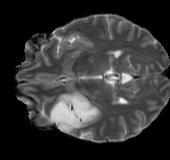

As we observe from the right image in Fig. 2, our BRM, both from MIMO and SISO settings, predicts the performance of dedicated models with a high correlation. We further choose the best three , and perform the last stage of fine-tuning accordingly to (6). A visual evaluation on real data is shown in Fig. 3. For simulated data, please refer to the Supplemental Material section.

Base on the best performing , we perceive that among , , and FLAIR, the results are best when is sampled the most. We suggest that this makes intuitive sense as images provide the best contrast out of the three sequences, which can compensate for the details lost in other images. The same observation can be made on the simulated data, where both and FLAIR show good contrast. When the time setting is changed to non-uniformity, we can see that our search for the best sampling strategy reflects the change. is sampled more as a result of faster acquisition time, while is still sufficiently sampled.

| Sequence | LR | SISO | MIMO | MIMO tuned | GT |

|---|---|---|---|---|---|

(a) 34.38/0.9371

(a) 34.38/0.9371

|

(b) 42.42/0.9883

(b) 42.42/0.9883

|

(c) 44.60/0.9920

(c) 44.60/0.9920

|

(d) 45.50/0.9940

(d) 45.50/0.9940

|

(e) PSNR/SSIM

(e) PSNR/SSIM

|

|

(f) 29.74/0.8903

(f) 29.74/0.8903

|

(g) 36.25/0.9734

(g) 36.25/0.9734

|

(h) 36.42/0.9752

(h) 36.42/0.9752

|

(i) 37.70/0.9832

(i) 37.70/0.9832

|

(j) PSNR/SSIM

(j) PSNR/SSIM

|

|

(k) 39.89/0.9311

(k) 39.89/0.9311

|

(l) 43.94/0.9864

(l) 43.94/0.9864

|

(m) 44.74/0.9883

(m) 44.74/0.9883

|

(n) 45.49/0.9894

(n) 45.49/0.9894

|

(o) PSNR/SSIM

(o) PSNR/SSIM

|